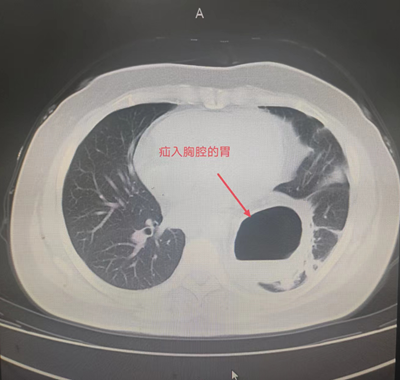

患者辛某,今年85岁,1年前患者因反酸、进食后反复呕吐于外院就诊。胸腹部CT检查提示:膈疝。胃十二指肠镜检查提示:食管外压性改变,膈疝,食管裂孔疝。患者长期营养不良,无法经口进食,只能通过鼻饲-空肠营养管置入进行营养,近日因营养管再次出现导管堵塞,随后被家人紧急送往六合彩生肖住院治疗。住院后进一步检查诊断食管裂孔疝、肺部感染,既往患有脐疝、胸椎手术史,合并心律失常、低氧血症、代谢性酸中毒、肺大疱、心脏瓣膜疾病、左侧颈动脉斑块形成、腔隙性脑梗塞等老年病史。

由于患者年事已高,病情复杂,手术难度极高。普外科主任田德福充分考虑到患者年龄、病情实际,先组织科室任斌、尹超、杨洲明、何慢等专家进行危重症患者治疗方案讨论。随后联系医务科组织全院多学科MDT讨论,根据全院MDT多科室会诊结果制定了周密的手术计划,并针对高龄患者可能出现的并发症做好各类突发应急准备。在麻醉手术部、手术室的全力配合下,普外科专家团队在全麻腹腔镜下成功为老人实施了食管裂孔疝、膈疝、脐疝三疝同时手术,术中探及食管裂孔疝,直径约4cm,其旁左侧直径约7cm大小膈疝,食管裂孔疝内容物为小网膜组织,膈疝内容物为胃底、胃体大部及大网膜组织。脐疝直径约3cm大小。腹腔镜下进行食管裂孔疝、膈疝无张力修补及脐疝修补术。手术顺利,术中患者生命体征基本稳定。术后在全科医护人员的治疗和精心护理下,逐渐进行经口进流食、半流食。床上活动、渐下床活动。复查各项指标渐正常。胃肠功能恢复正常,于6月14日痊愈出院,近日回访患者一般情况良好。